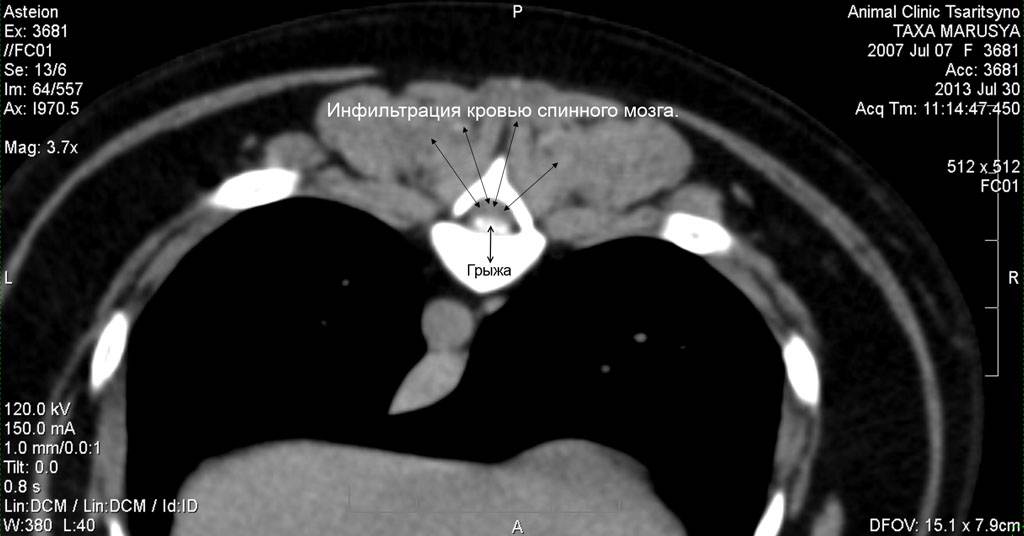

Рис. 2. КТ изображение в мягкотканом окне. Эта же собака. Аксиальная (поперечная) проекция. В просвете СМ канала видна грыжа, которая сдавливает спинной мозг, вызывая нарушение его функции. Данное животное после обследования успешно прооперировано. Реабилитация прошла успешно. Функции задних конечностей восстановились полностью